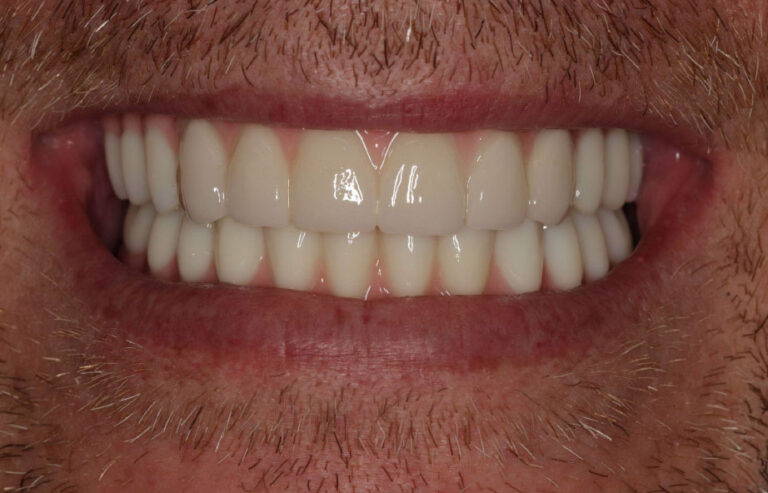

Final Smile Delivery

Once healing is complete, the final zirconia full-arch restoration is delivered. The patient returns to you for:

- Prototype approval

- Final prosthetic delivery

- Bite verification